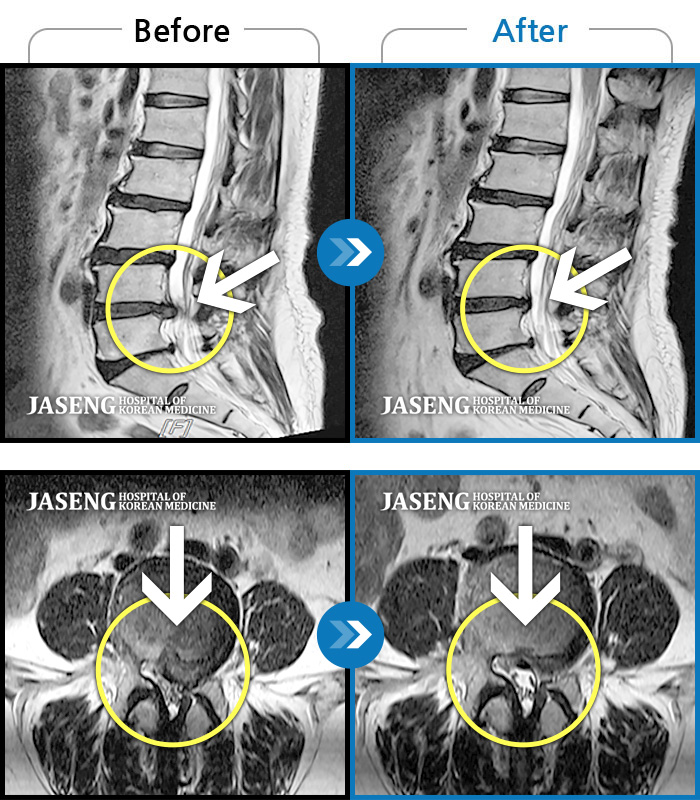

MRI 치료사례

허리 골반 통증, 왼쪽 허벅지부터 발등까지 저리고 당김